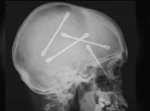

Et oui, les cerveaux ça existe !